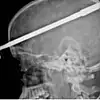

Zıpkını temizlemesi sırasında yanlışlıkla ateş etmesi sonucu sol gözünden kafasına 15 santimetre uzunluğunda mızrak saplanan Coutinho, olay sonrası bilincini kaybetmeden halasına bağırmayı başardı. Hemen hastaneye kaldırılan Coutinho, tedavi altına alındı. Doktorlar Coutinho’nun gözünden 10 saatlik operasyon sonrası mızrağı çıkarmayı başardı. Coutinho’nun beyninde bir hasar oluşmadığını ifade eden doktorlar, şanslı adamın sol gözünü fiziki olarak kurtardıklarını fakat görme yetisini kaybettiğini açıkladılar